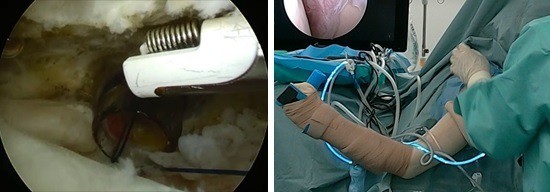

• 距骨骨軟骨損傷(離断性骨軟骨炎)

スポーツ整形

距骨骨軟骨損傷(離断性骨軟骨炎)